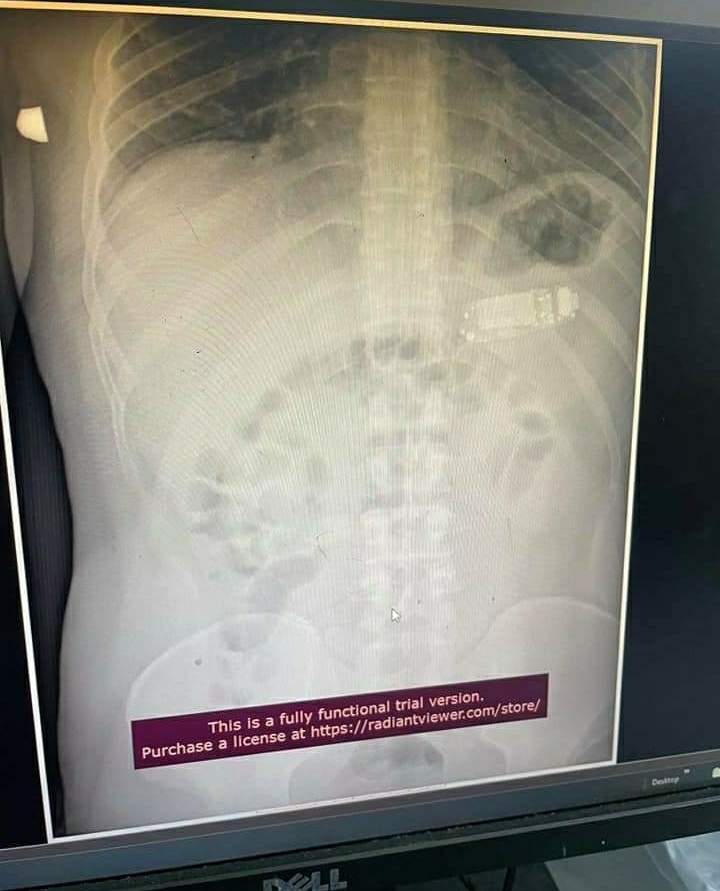

Një pacient i moshës 33 vjeçare nga Kosova, në rrethana të pasqaruara ka përbirë një telefon, raporton Albinfo.ch.

E telefoni i markës Nokia arriti t’i largohej me sukses nga doktorët e QKUK-së.

Dr.Naim Telaku, i cili edhe ka ndarë imazhe ka bërë të ditur se pacienti telefonin e kishte përbirë para 4 ditësh.

“Mashkulli 33 vjec para 4 ditesh kishte perbire nje telefon te vogel. Me rruge endoskopike, pra pa e prere lukthin, nxorrem telefonin e ndare ne tri pjese. Pa komplikime”, shkruan doktor Telaku, përcjell Albinfo.ch.